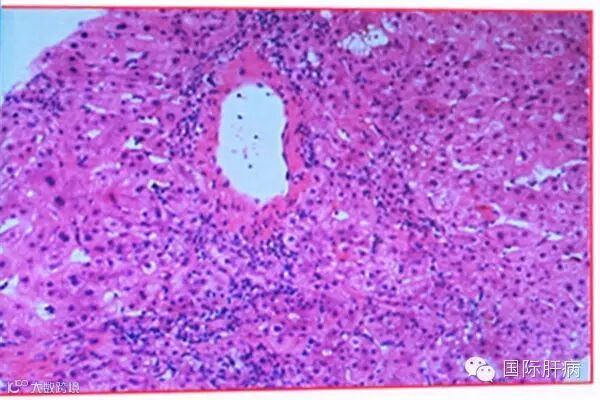

5)小叶中央坏死

研究显示,17.5%的AIH患者在肝活检组织中可出现小叶中央(第三区)坏死,可能是AIH急性发作的表现之一。它可以单独出现,也可伴随界面性肝炎和较重的门管区炎症。患者往往伴有高胆红素血症,及时的免疫抑制治疗缓解后小叶中央坏死可完全消失。

小叶中央坏死(HE,200倍)